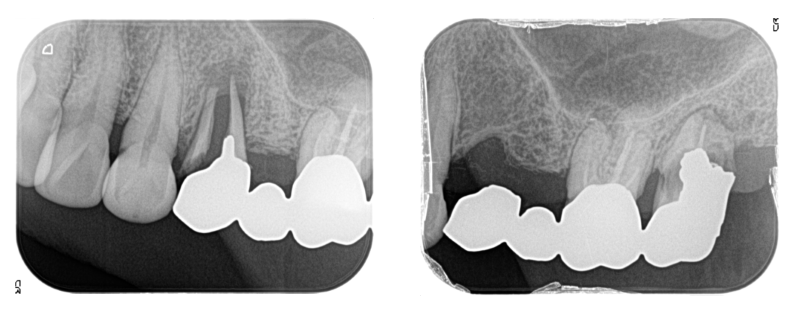

左上奥歯にブリッジが入っていましたが、歯根破折して

保存できない状態だったため、3本とも抜歯になりました。

抜歯後、3ヶ月歯肉の治りを待ちます。

レントゲンとCTで、上顎洞という鼻とつながっている空洞の形を診査し

骨の厚さが少し足りないことが分かったため、上顎洞粘膜を挙上して

骨造成することにしました。

3本埋入しています。1本はGBRも併用しています。

3本とも上顎洞粘膜を挙上しています。

挙上は水圧で行い、挙上した部分は生理食塩水と血液で満たされています。

その血液が骨に変わります。

異物を入れないため、アレルギー反応も無く、非常に安全性の高い方法です。

この状態で4ヶ月ほど待ちます。